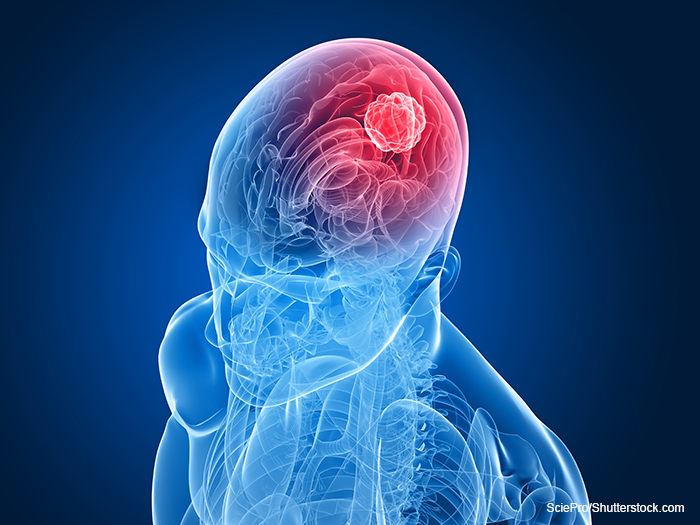

STTR Award to LSU Health New Orleans Spin-Out Company to Develop New Class of Anticancer Drugs for Glioblastoma

Glioblastoma multiforme accounts for nearly half of malignant brain tumors. The median overall survival is only about 15 months.“The main objective of this research is to develop, test and select the most effective metabolic drug candidate, which will initially be used in dogs with cancer whose owners are seeking treatment,” adds Dr. Reiss. “The safety and efficacy data will ultimately help us prepare for a human glioblastoma clinical trial.”